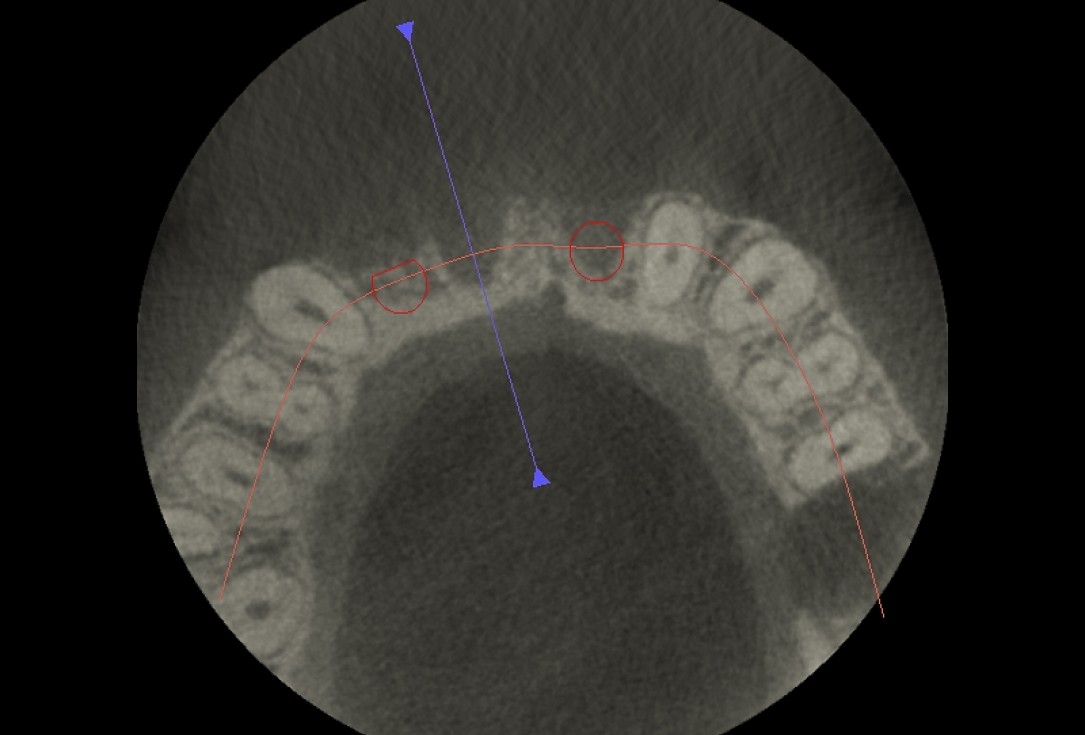

03/17 - Vestibular defect of hard tissue visible in CBCT examination with planned position of future implants

Block augmentation with maxgraft® block & mucoderm® - Dr. K. Chmielewski